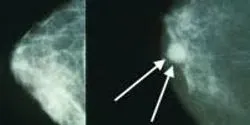

This is an important discovery for breast cancer patients with poor overall survival and disease-free survival (DFS) prognose